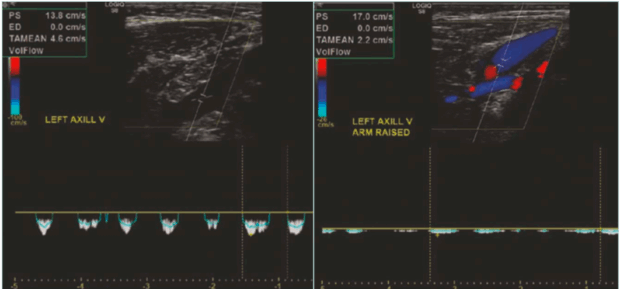

DUS is a primary, noninvasive modality and the initial imaging test of choice in suspected VTOS. A standard venous DUS may miss the diagnosis if performed only in the neutral position. Therefore, a comprehensive dynamic DUS is essential. This entails examining the axillary-subclavian vein in both neutral and provocative positions, such as with the arm abducted, elevated, or placed in military brace posture. The dynamic scan assesses for the following: i) positional compression with loss or reduction in venous waveform phasicity (Figure 6); ii) retrograde flow or cessation of flow in abduction; iii) visualization of thrombus, echogenic webs, or wall thickening; and iv) presence of prominent collaterals.

Figure 6. Presence of respiratory phasicity in the spectral wave of the axillary vein in the neutral position (left image) and loss of the respiratory phasicity in the abduction position (right image).

Dynamic DUS is operator-dependent and must be interpreted with care. Its sensitivity for detecting acute thrombosis is high, but its ability to assess external compression hinges on precise positioning, patient cooperation, and real-time visualization. High-resolution probes and color Doppler enhancement improve diagnostic yield.